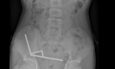

Η διαδικασία της σίτισης γίνεται ως εξής: Ένας λεπτός σωλήνας (που ονομάζεται ρινογαστρικός καθετήρας) περνάει από τη μύτη για να φτάσει στο στομάχι και στη συνέχεια με μία σύριγγα που εφαρμόζεται στο εξωτερικό άκρο χορηγείται νερό και φαγητό.

Η σίτιση μέσω ρινογαστρικού καθετήρα είναι μία ιατρική πράξη, η οποία γίνεται καθημερινά στα νοσοκομεία προκειμένου να καλυφθούν οι θερμιδικές ανάγκες ασθενών, οι οποίοι δεν μπορούν να φάνε, όπως για παράδειγμα με διαταραχές της κατάποσης.